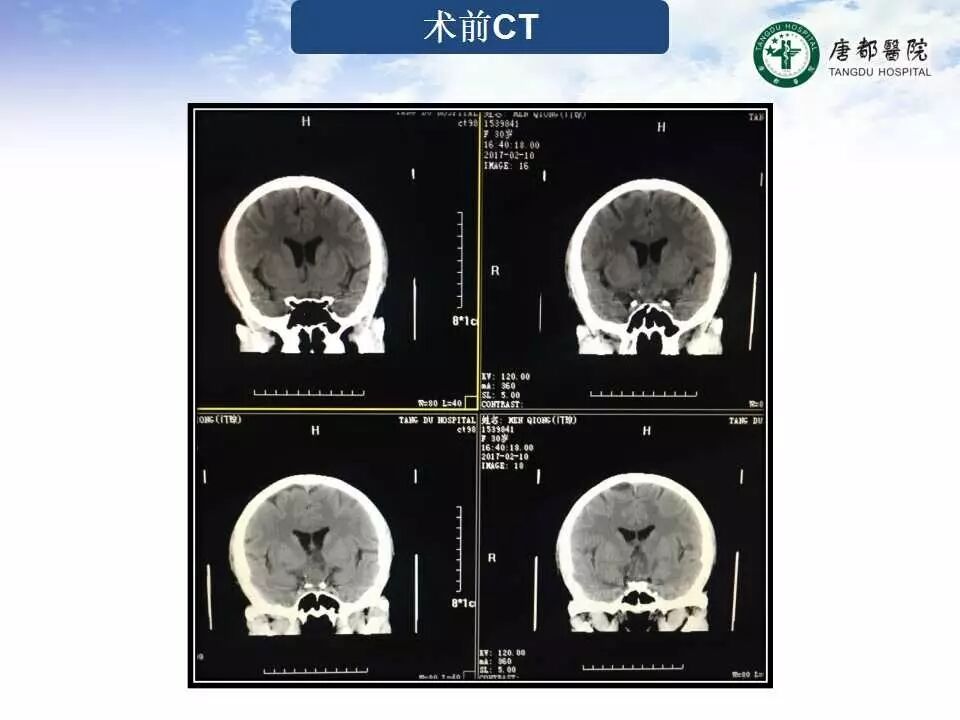

Case 1